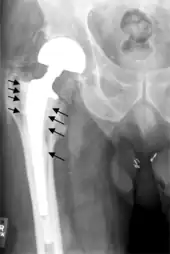

Loosening

Hip prosthesis displaying aseptic loosening (arrows)

Hip prosthesis zones according to DeLee and Charnley,[27] and Gruen.[28] These are used to describe the location of for example areas of loosening.

On radiography, it is normal to see thin radiolucent areas of less than 2 mm around hip prosthesis components, or between a cement mantle and bone. These may indicate loosening of the prosthesis if they are new or changing, while areas greater than 2 mm may be harmless if they are stable.[29] The most important prognostic factors of cemented cups are absence of radiolucent lines in DeLee and Charnley zone I, as well as adequate cement mantle thickness.[30] In the first year after insertion of uncemented femoral stems, it is normal to have mild subsidence (less than 10 mm).[29] The direct anterior approach has been shown to itself be a risk factor for early femoral component loosening.[31][32][33]